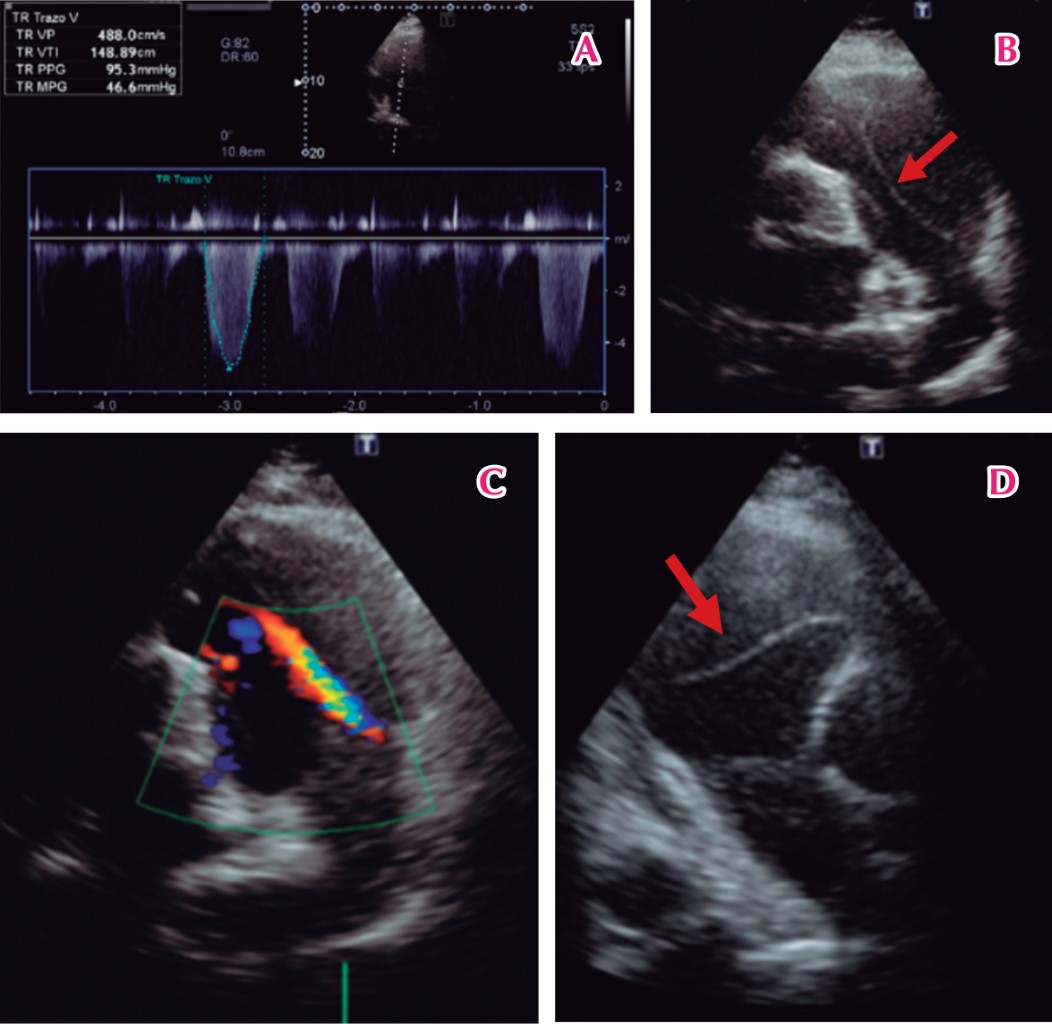

Objetivo: Describir la presentación de una disección de arteria pulmonar a la Unidad de Urgencias, la secuencia de eventos y revisión de la literatura. Reporte de caso: Paciente femenino de 59 años con cardiopatía chagásica conocida, quien acudió a urgencias por un episodio de dolor torácico repentino punzante y disnea progresiva, que evolucionó rápidamente a choque cardiogénico. Una radiografía de tórax informó un ensanchamiento severo del mediastino y cardiomegalia; por tanto, se realizó una angiotomografía torácica para descartar síndrome aórtico agudo, en la que se diagnosticó un aneurisma disecante de arteria pulmonar. El ecocardiograma transtorácico mostró un colgajo de la íntima a nivel de la arteria pulmonar y una dilatación severa. La paciente falleció en menos de 4 horas desde su llegada a urgencias sin poder acceder a tratamiento quirúrgico debido a la rápida evolución. Conclusión: La disección de la arteria pulmonar es una enfermedad rara, con una alta tasa de mortalidad. El manejo óptimo requiere un diagnóstico rápido con múltiples técnicas de imagen. Falta información sobre este tema.

Figura 2